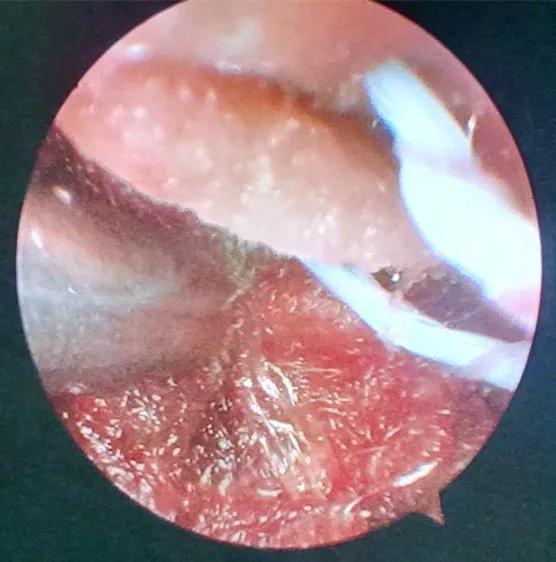

近日,一位六十岁的男性,在家中突发头痛、呕吐、左侧肢体瘫软无力摔倒在地,被家人急送市中心医院急诊科,急诊接诊后发现患者处于昏迷状态,遂急查颅脑CT并请神经外科会诊。CT结果显示患者小脑出血40毫升,即刻收住神经外科住院。

患者病情危重,出血点位于后颅窝靠近天幕,位置狭小、深在、靠近脑干、直视困难,应用普通手术操作困难,容易损伤脑干,血肿也不容易彻底清除。主管主任医师王占尧对该患者进行了详细的查体后,与治疗小组商议手术方案。为进一步减少小脑皮层损伤、降低颅脑创伤,王占尧主任医师决定对该患者使用内镜辅助清除血肿。

诊疗小组在王占尧主任医师的带领下,制定了详尽的手术方案。由王占尧主任医师主刀、贺中正医师辅助为患者实施了神经内镜下血肿清除术,患者术后恢复良好。